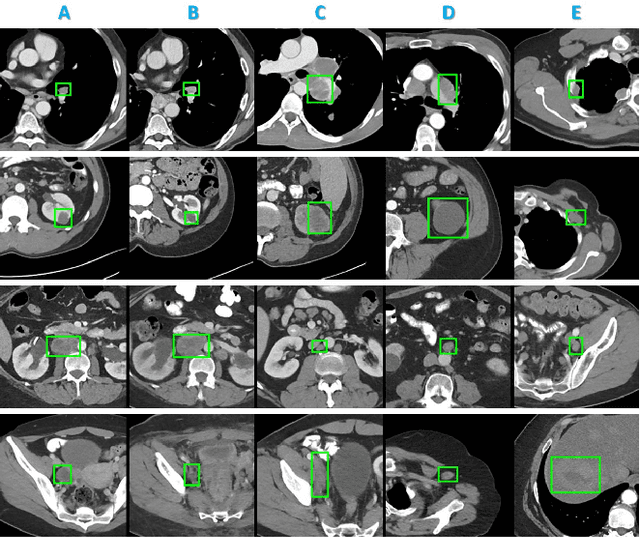

Abstract:Radiologists in their daily work routinely find and annotate significant abnormalities on a large number of radiology images. Such abnormalities, or lesions, have collected over years and stored in hospitals' picture archiving and communication systems. However, they are basically unsorted and lack semantic annotations like type and location. In this paper, we aim to organize and explore them by learning a deep feature representation for each lesion. A large-scale and comprehensive dataset, DeepLesion, is introduced for this task. DeepLesion contains bounding boxes and size measurements of over 32K lesions. To model their similarity relationship, we leverage multiple supervision information including types, self-supervised location coordinates and sizes. They require little manual annotation effort but describe useful attributes of the lesions. Then, a triplet network is utilized to learn lesion embeddings with a sequential sampling strategy to depict their hierarchical similarity structure. Experiments show promising qualitative and quantitative results on lesion retrieval, clustering, and classification. The learned embeddings can be further employed to build a lesion graph for various clinically useful applications. We propose algorithms for intra-patient lesion matching and missing annotation mining. Experimental results validate their effectiveness.